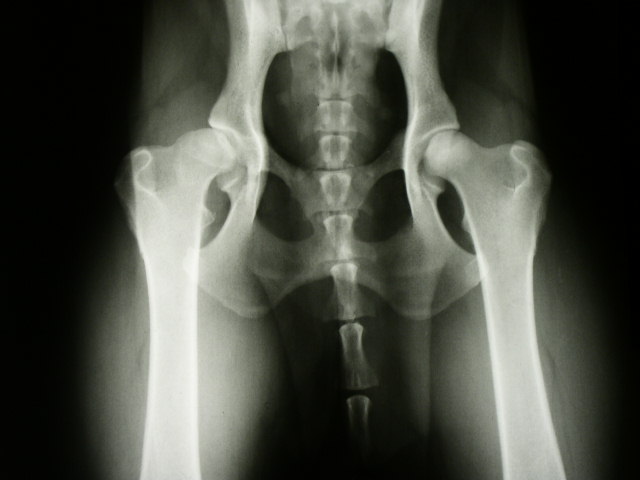

Pro zhotovení oficiálního snímku je nutná sedace psa k vyblokování svalového tonu a pro umožnění optimální polohy. Snímek se zhotovuje na zádech, s nataženými a mírně vtočenými pánevními končetinami, kyčelní klouby, kolena i hlezenní klouby uvedeme do extenze. Končetiny musí probíhat paralelně, tak, aby čéšky byly na snímku uprostřed stehenní kosti. Pánev nesmí být rotovaná.

Na snímku se hodnotí tvar hlavice, hloubka zanoření hlavice, symetrie kloubní štěrbiny, Norberg – Olssonův úhel, degenerativní změny.

Podle FCI se hodnotí DKK takto:

STUPEŇ  DKK

POPIS

A

negativní, bez příznaků dysplazie

Kongruentní hlavice a acetabulum, Norberg – Olssonův úhel je 105 stupňů a více. Kraniolaterální okraj acetabula je ostře ohraničený a mírně zaoblený, kloubní štěrbina je úzká a pravidelná, střed hlavice leží mediálně od dorzálního okraje acetabula

B

hraniční dysplazie, přechodný stupeň

Mírná inkongruence, střed hlavice leží mediálně od DOA, N-O úhel je 105 a více. Nebo jsou hlavice femuru a acetabulum kongruentní a úhel je nižší než 105.

C

mírná dysplazie

Kloubní plochy jsou inkongruentní, N-O úhel je větší než 100. Kraniolaterální okraj je mírně oploštělý, střed hlavice je na úrovni DOA. Mírná artróza.

D

střední dysplazie

Výrazná inkongruence se subluxací, střed hlavice leží laterálně od DOA. N-O úhel je více než 90 stupňů. Kraniolaterální okraj acetabula je oploštělý a/nebo jsou zřetelné příznaky artrózy.

E

těžká dysplazie

Výrazné změny v kyčelním kloubu jako subluxace nebo luxace, N-O úhel je méně než 90 stupňů.Výrazné oploštění kraniolaterálního okraje acetabula , deformace hlavice, další příznaky artrózy.

Existují různá hodnotící schémata, mezi nejnovější patří to, kdy je hodnoceno sedm parametrů , každý počtem bodů od 0 do 4 . Po vyhodnocení se jednotlivé body sečtou a stupni A odpovídají 0 – 2 body - zdravý kloub, stupni B 3 - 7 bodů - přechodná forma, 8 – 14 bodů nízký stupeň dysplazie C, 15 – 21 bodů střední stupeň D, 22 – 28 bodů vysoký stupeň dysplazie E. Parametr 1.1,1.2,1.3 popisují acetabulum, 2.1,2.2 hlavici a krček femuru, 3 a 4 vzájemné postavení hlavice a acetabula - kongruitu kloubní štěrbiny a Norberg – Olssonův úhel.